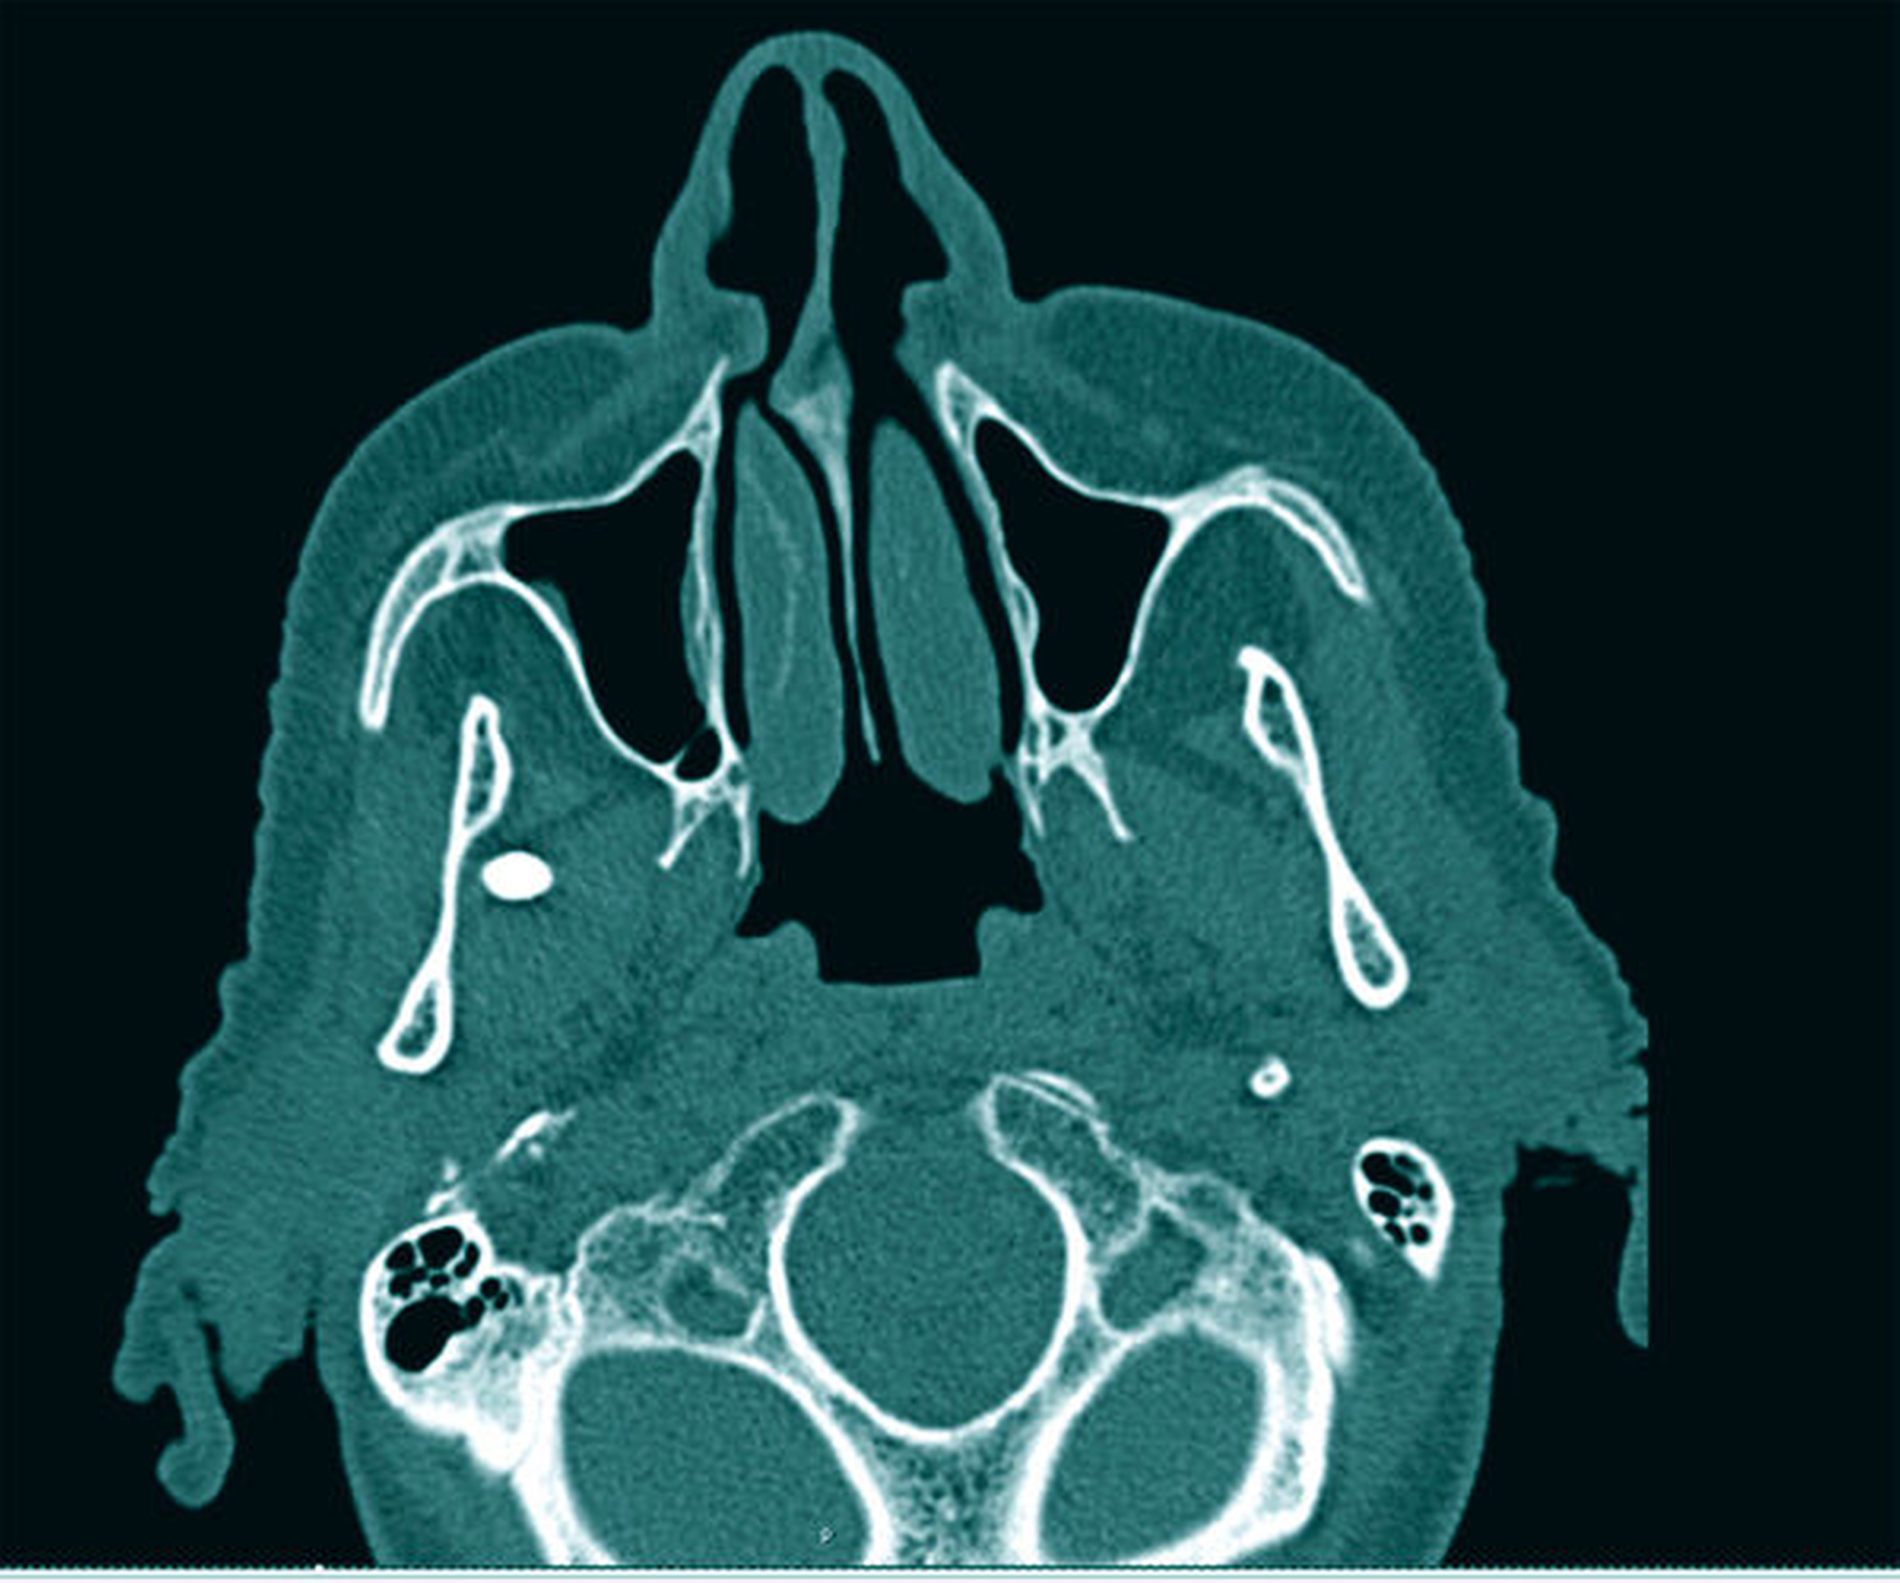

Auf der angefertigten Computertomografie war ein zur Geschichte der Patientin passendes Objekt in der Form einer Griffelspitze deutlich erkennbar, die im Spatium pterygomandibulare mit enger Lagebeziehung zum Nervus mandibularis lokalisiert war (Abbildungen 2 und 3).